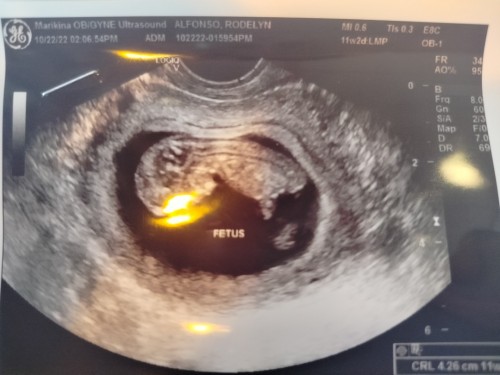

Okey lng ba uminom ng gamot sa hepa b Resita nmn sya ng ob ko 3month pregnant na po 🤰🤰🤰🤰🤰🤰🤰

Pregnant #